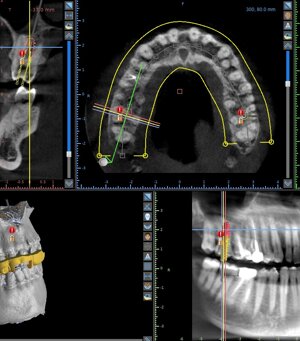

Nella clinica è presente un’apparecchiatura digitale che permette di effettuare radiografie panoramiche in 2D e Tac Cone Beam 3d, utili per visualizzare l’intera arcata nell’immediato.

PROGETTAZIONE IMPLANTOLOGIA A SEGUITO DA TAC CONE-BEAM E IMPRONTA DIGITALE

Un attenta progettazione che parte dall'impronta digitale cii permette di pianificare gli interventi di chirurgia computer guidata non invasiva chirurgicamente.A cura dell' Implantologo Dr Francesco Froio ( Ordine dei Medici e Odontoiatri di Roma)